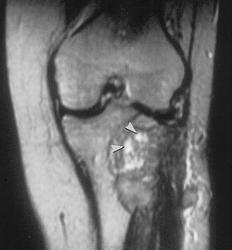

Гигантоклеточная опухоль.

Злокачественная гигантоклеточная  опухоль возникает из доброкачественной (частота 10-20%). После операции возможно появление рецидива опухоли.